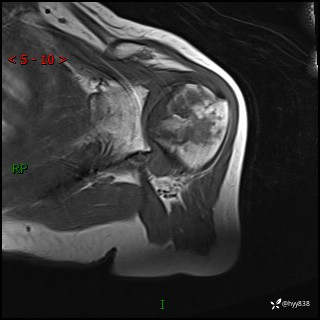

肱骨MRI平扫(axi T1WI+cor T2WI-fs)+CE-fs(COR+SAG)

现病史:患者1月前无明显诱因出现左肩关节疼痛,于2024.07.31就诊于我院骨科门诊完善左肩关节MR:左肱骨头信号异常,肿瘤?建议进一步检查。左肩关节积液。左腋窝淋巴结增大。今为求明确诊断就诊我科,门诊以“骨质破坏”收入我科。 起病以来,精神食欲睡眠尚可,大小便正常,体力体重无明显变化。

既往史:系统性红斑狼疮10余年,目前行强的松、羟氯喹治疗